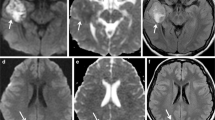

Tumor progression. MRI of the brain obtained in a 62 year old patient with temporal lobe glioblastoma, status post-surgery, concurrent chemoradiation, and six cycles of adjuvant temozolomide, reveals a new lesion in the left thalamus. a) T2/FLAIR image shows hyperintensity in the left thalamus, b) with slight enhancement noted on corresponding T1 post-contrast image. c) There is a minimal increase in perfusion (permeability) as depicted by DCE, and d) DSC demonstrates an increase in perfusion (rCBV >2). e and f) MR spectroscopy reveals an increased choline-to-creatinine ratio (Cho:Cr >2). Together, these findings suggest this lesion represents a high-grade glioma such as glioblastoma

Structural imaging in the form of conventional MRI is the standard imaging modality for assessing treatment response. Although associated with high sensitivity, its use is limited in discerning PsP from PD, as post-treatment contrast enhancement is non-specific (Fig. 1a, 2a, b).

DSC MRI utilizes the T2*-weighted MRI signal drop caused by susceptibility effect of gadolinium-based contrast in brain tissue; the typical hemodynamic parameter include rCBV, relative peak height (rPH), and percentage of signal-intensity recovery (PSR) [28•]. Typically, a higher rCBV value [28•] and hyperperfusion is found in recurrence, due to increased metabolic activity and neo-angiogenesis from increased (VEGF) expression [32–34]. A lower rCBV value [28•], hypoperfusion, and ischemia-related changes from occlusive vasculopathy are associated with treatment-induced necrosis and pseudoprogression [35]. A caution to interpreting rCBV values is that rapidly growing tumor may exceed its blood supply and result in necrosis or hypoperfusion [6] (Fig. 1c and Fig. 2d).

DCE MRI is a T1-based technique that reflects the overall perfusion, vascular permeability, and extracellular volume in tumors. There are few reports describing the application of the vascular permeability (K-trans) parameter, which is higher in tumor progression than treatment related changes, to differentiating PD from PsP; however, the quantification of hemodynamic parameters in DCE MRI is complex and prone to error. Further, DCE MRI is associated with poor temporal resolution and a limited area of lesion coverage [28•]. However, there are benefits to DCE MRI over DSC MRI, including better spatial resolution, which may provide an advantage for differentiating mixed lesion cases (Fig. 2d)

Magnetic Resonance Spectroscopy

Magnetic resonance spectroscopy (MRS) detects different metabolites in tissue [1], such as N-acetylaspartate (NAA), choline (Cho), creatinine (Cr), lipid, and lactate. MRS has been used to grade tumors (correlating with histologic outcomes) [28•], and may help discriminate PD from treatment-related effects based on the ratios of NAA, Cho and Cr [11, 28•]. High-grade gliomas demonstrate elevated Cho (due to increased cell membrane phospholipids)-to-Cr (Cho:Cr ratio >2) and decreased NAA; this is not seen in normal white matter or lesions related to treatment [1]. RT necrosis is associated with elevated lipid and lactate peaks [1], decreased NAA, and variable changes to Cho and Cr over time [6, 28•] (Fig. 1d and Fig. 2e, f)

Multi-modality functional imaging protocols have proven more successful in the quest to differentiate PD from PsP. One study reported that the ability to detect brain tumors increased from 68 % to 97 % when structural MRI was used along with FET-PET and MRS [46]. Another study reported strong discriminatory power with the use of MRS plus DWI [47]. Prat et al. suggested MRS and MRP as the most promising combination [48] for detecting recurrence, and discouraged the use of a single modality. Matsusue implemented a multiparametric protocol of diffusion imaging, perfusion imaging and MRS, and reported accuracy for differentiating PsP from PD significantly better than any single modality [49] (Figs. 1 and 2) This approach may be potentially limited by the low availability of scanners, high operative costs, and lack of coverage by insurance providers [28•].